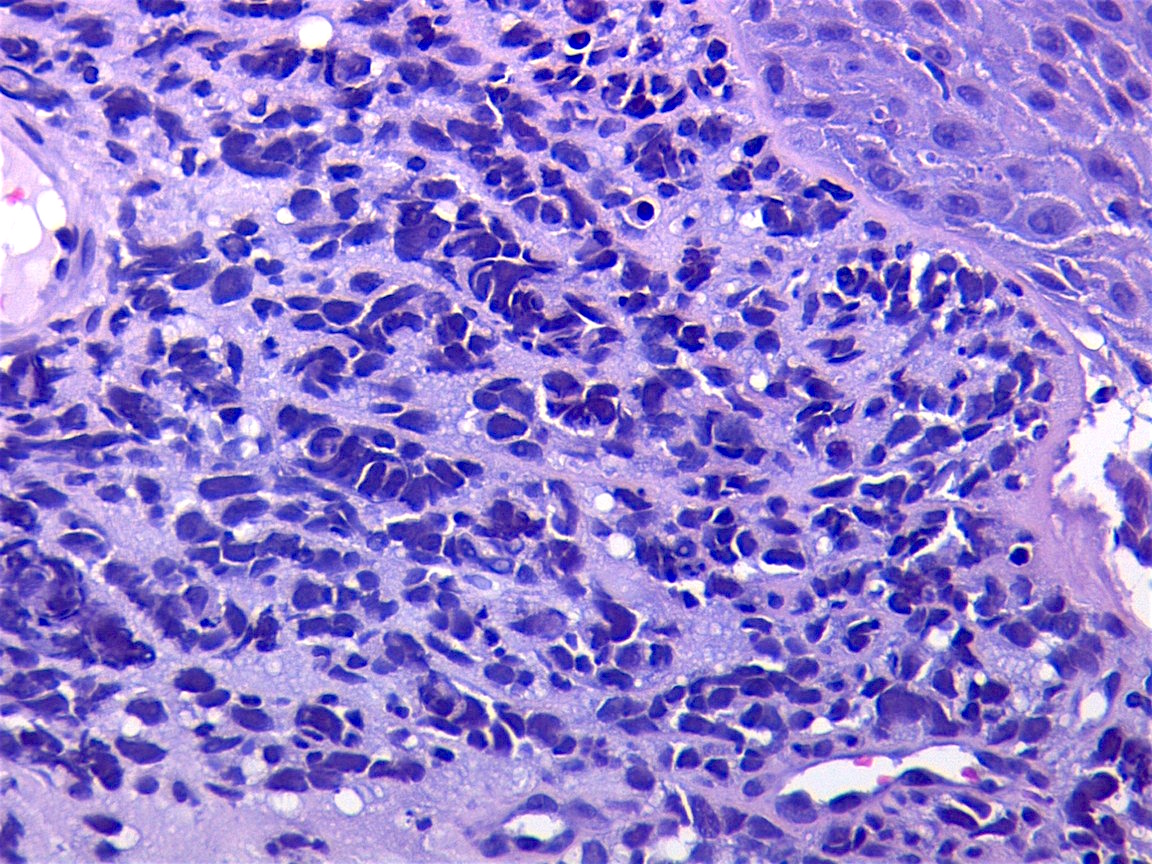

- Clinical and morphologic features: primitive hypercellular tumor with spindled to round shaped cells; mitotic activity and necrosis are common

- Composed of primitive mesenchymal cells that show variable degrees of skeletal muscle differentiation

- Sheets of small, stellate, spindled or round cells with scant or deeply eosinophilic cytoplasm and eccentric, small oval nuclei with a light chromatin pattern and inconspicuous nucleoli

- If densely cellular, may resemble solid alveolar rhabdomyosarcoma (Am J Clin Pathol 2013;140:82)

- Cells are undifferentiated, round or spindled with minimal cytoplasm, frequent mitotic figures

Microscopic (histologic) images

Contributed by Erdener Özer, M.D., Ph.D. and Mark R. Wick, M.D.

AFIP images - anaplastic rhabdomyosarcoma